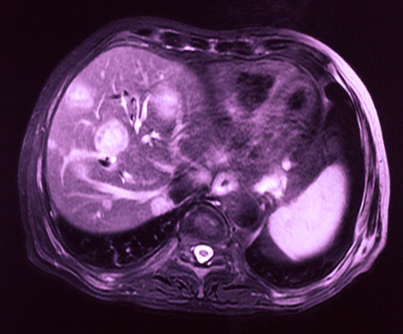

MRI of liver cancer; image © Hong xia / Shutterstock.com